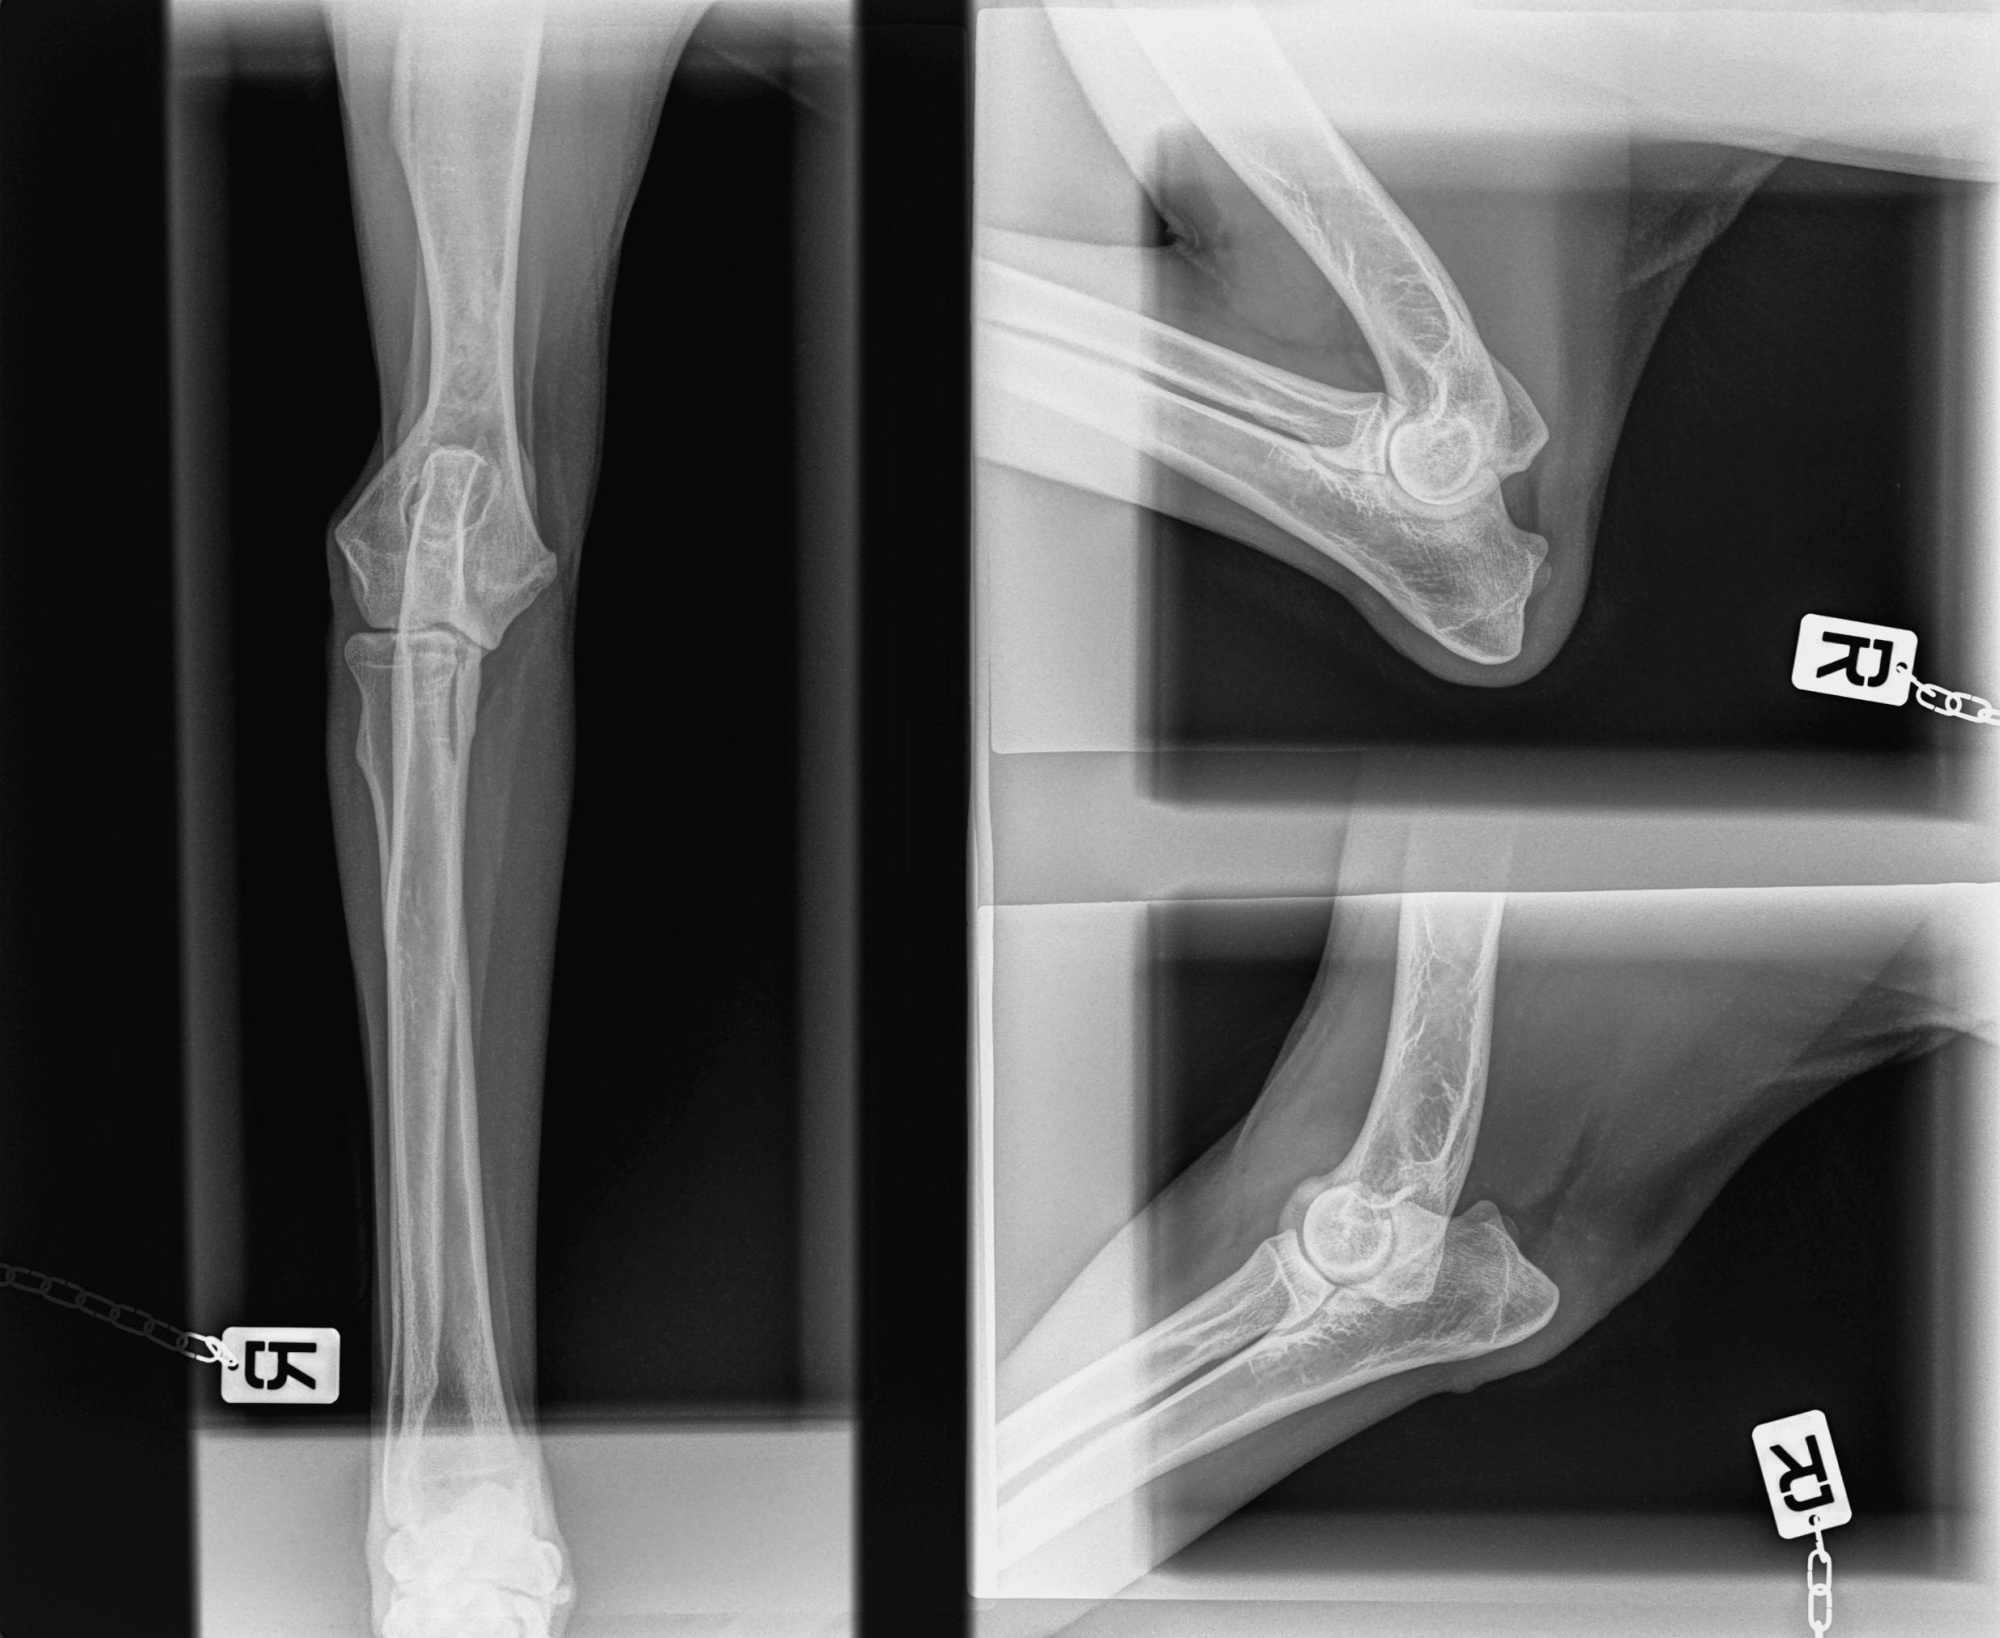

Установлены: DR-панель AGFA DXD-40G со стойкой, рентген аппарат Porta 100 HF, принтер для печати рентгеновских снимков AGFA DryStar 5302.